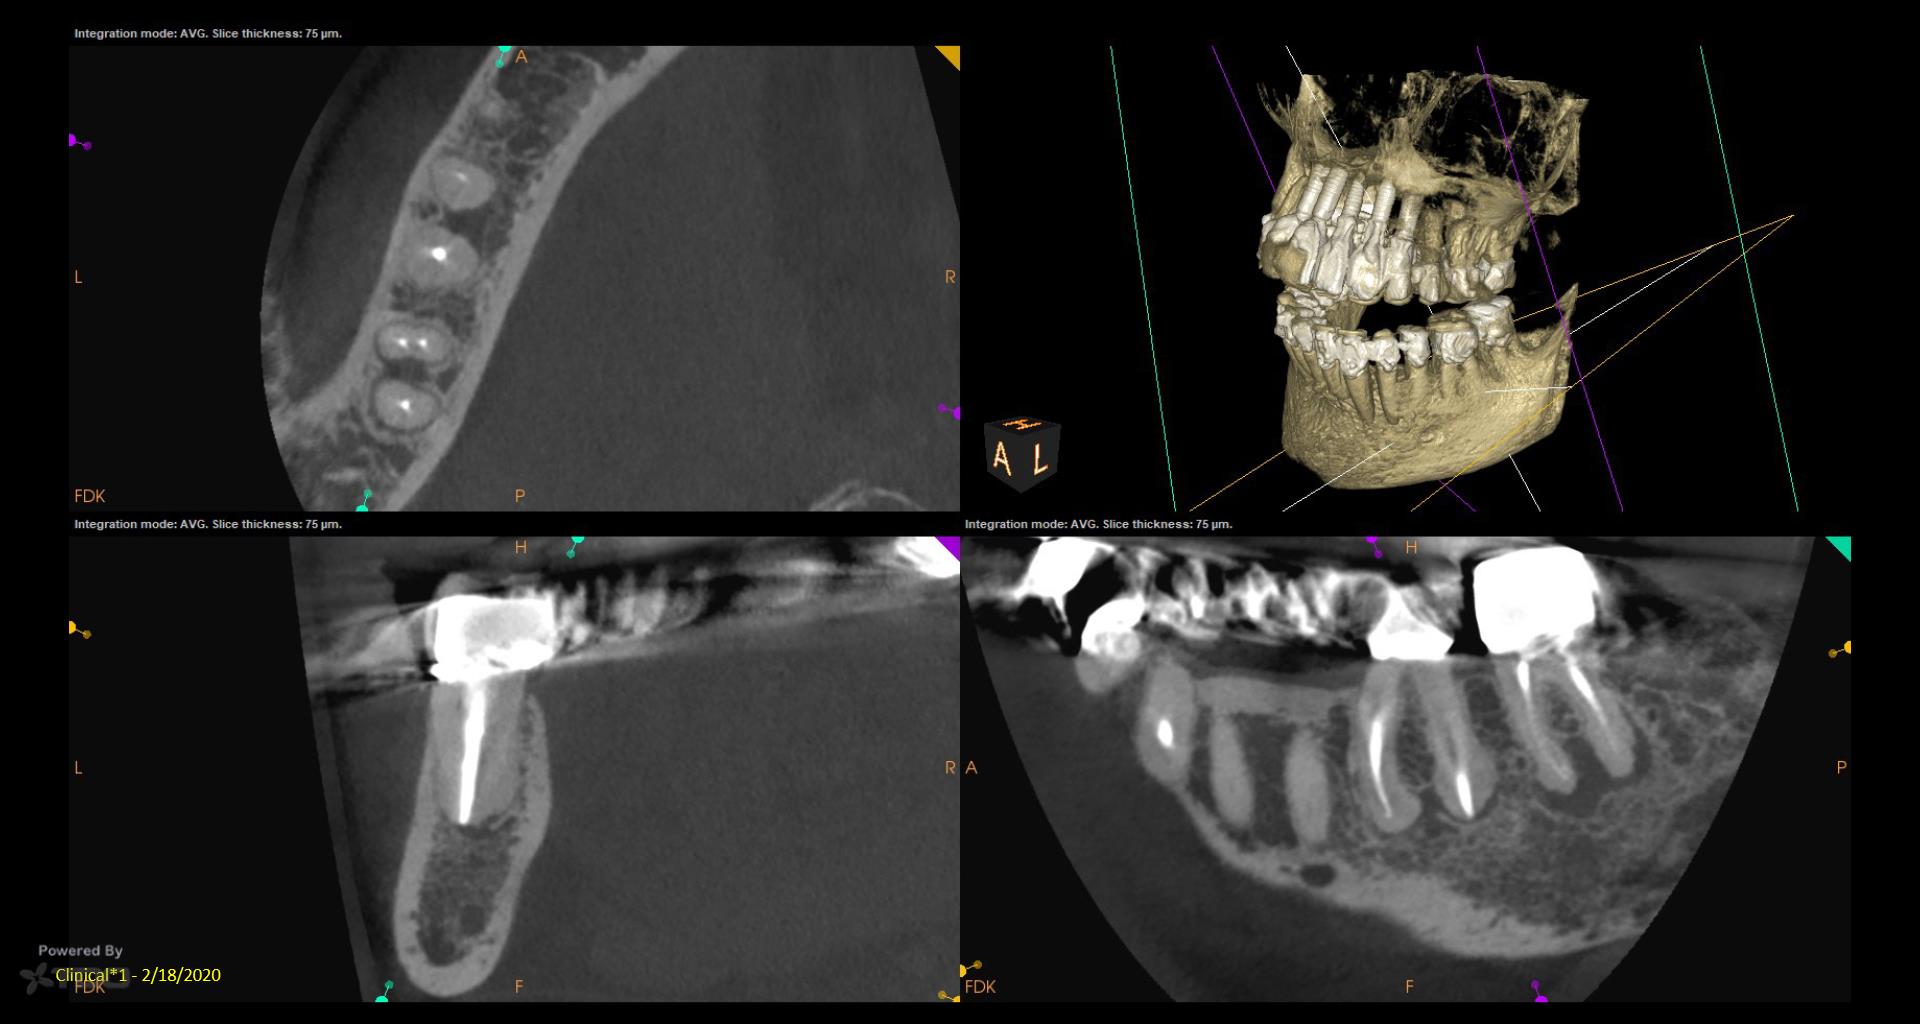

I did a retreat #19 15 years ago. Today symptom free but #18 looks suspicious and maybe even #19……. Perfect case for monitoring….not anxious to do another retreat… gbc

My experience with retreat #19 fifteen years ago was transformative, and I’m grateful to be symptom-free today. However, I’ve noticed convalescent hospital some concerning signs with #18 and possibly #19, which makes me cautious. While I appreciate the value of retreats, I’m not eager to dive back in just yet. Monitoring feels essential now.